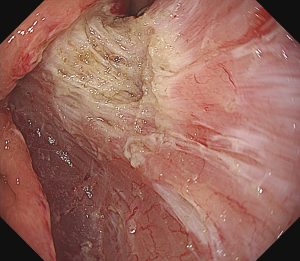

早期大腸癌(LST-G)ESD